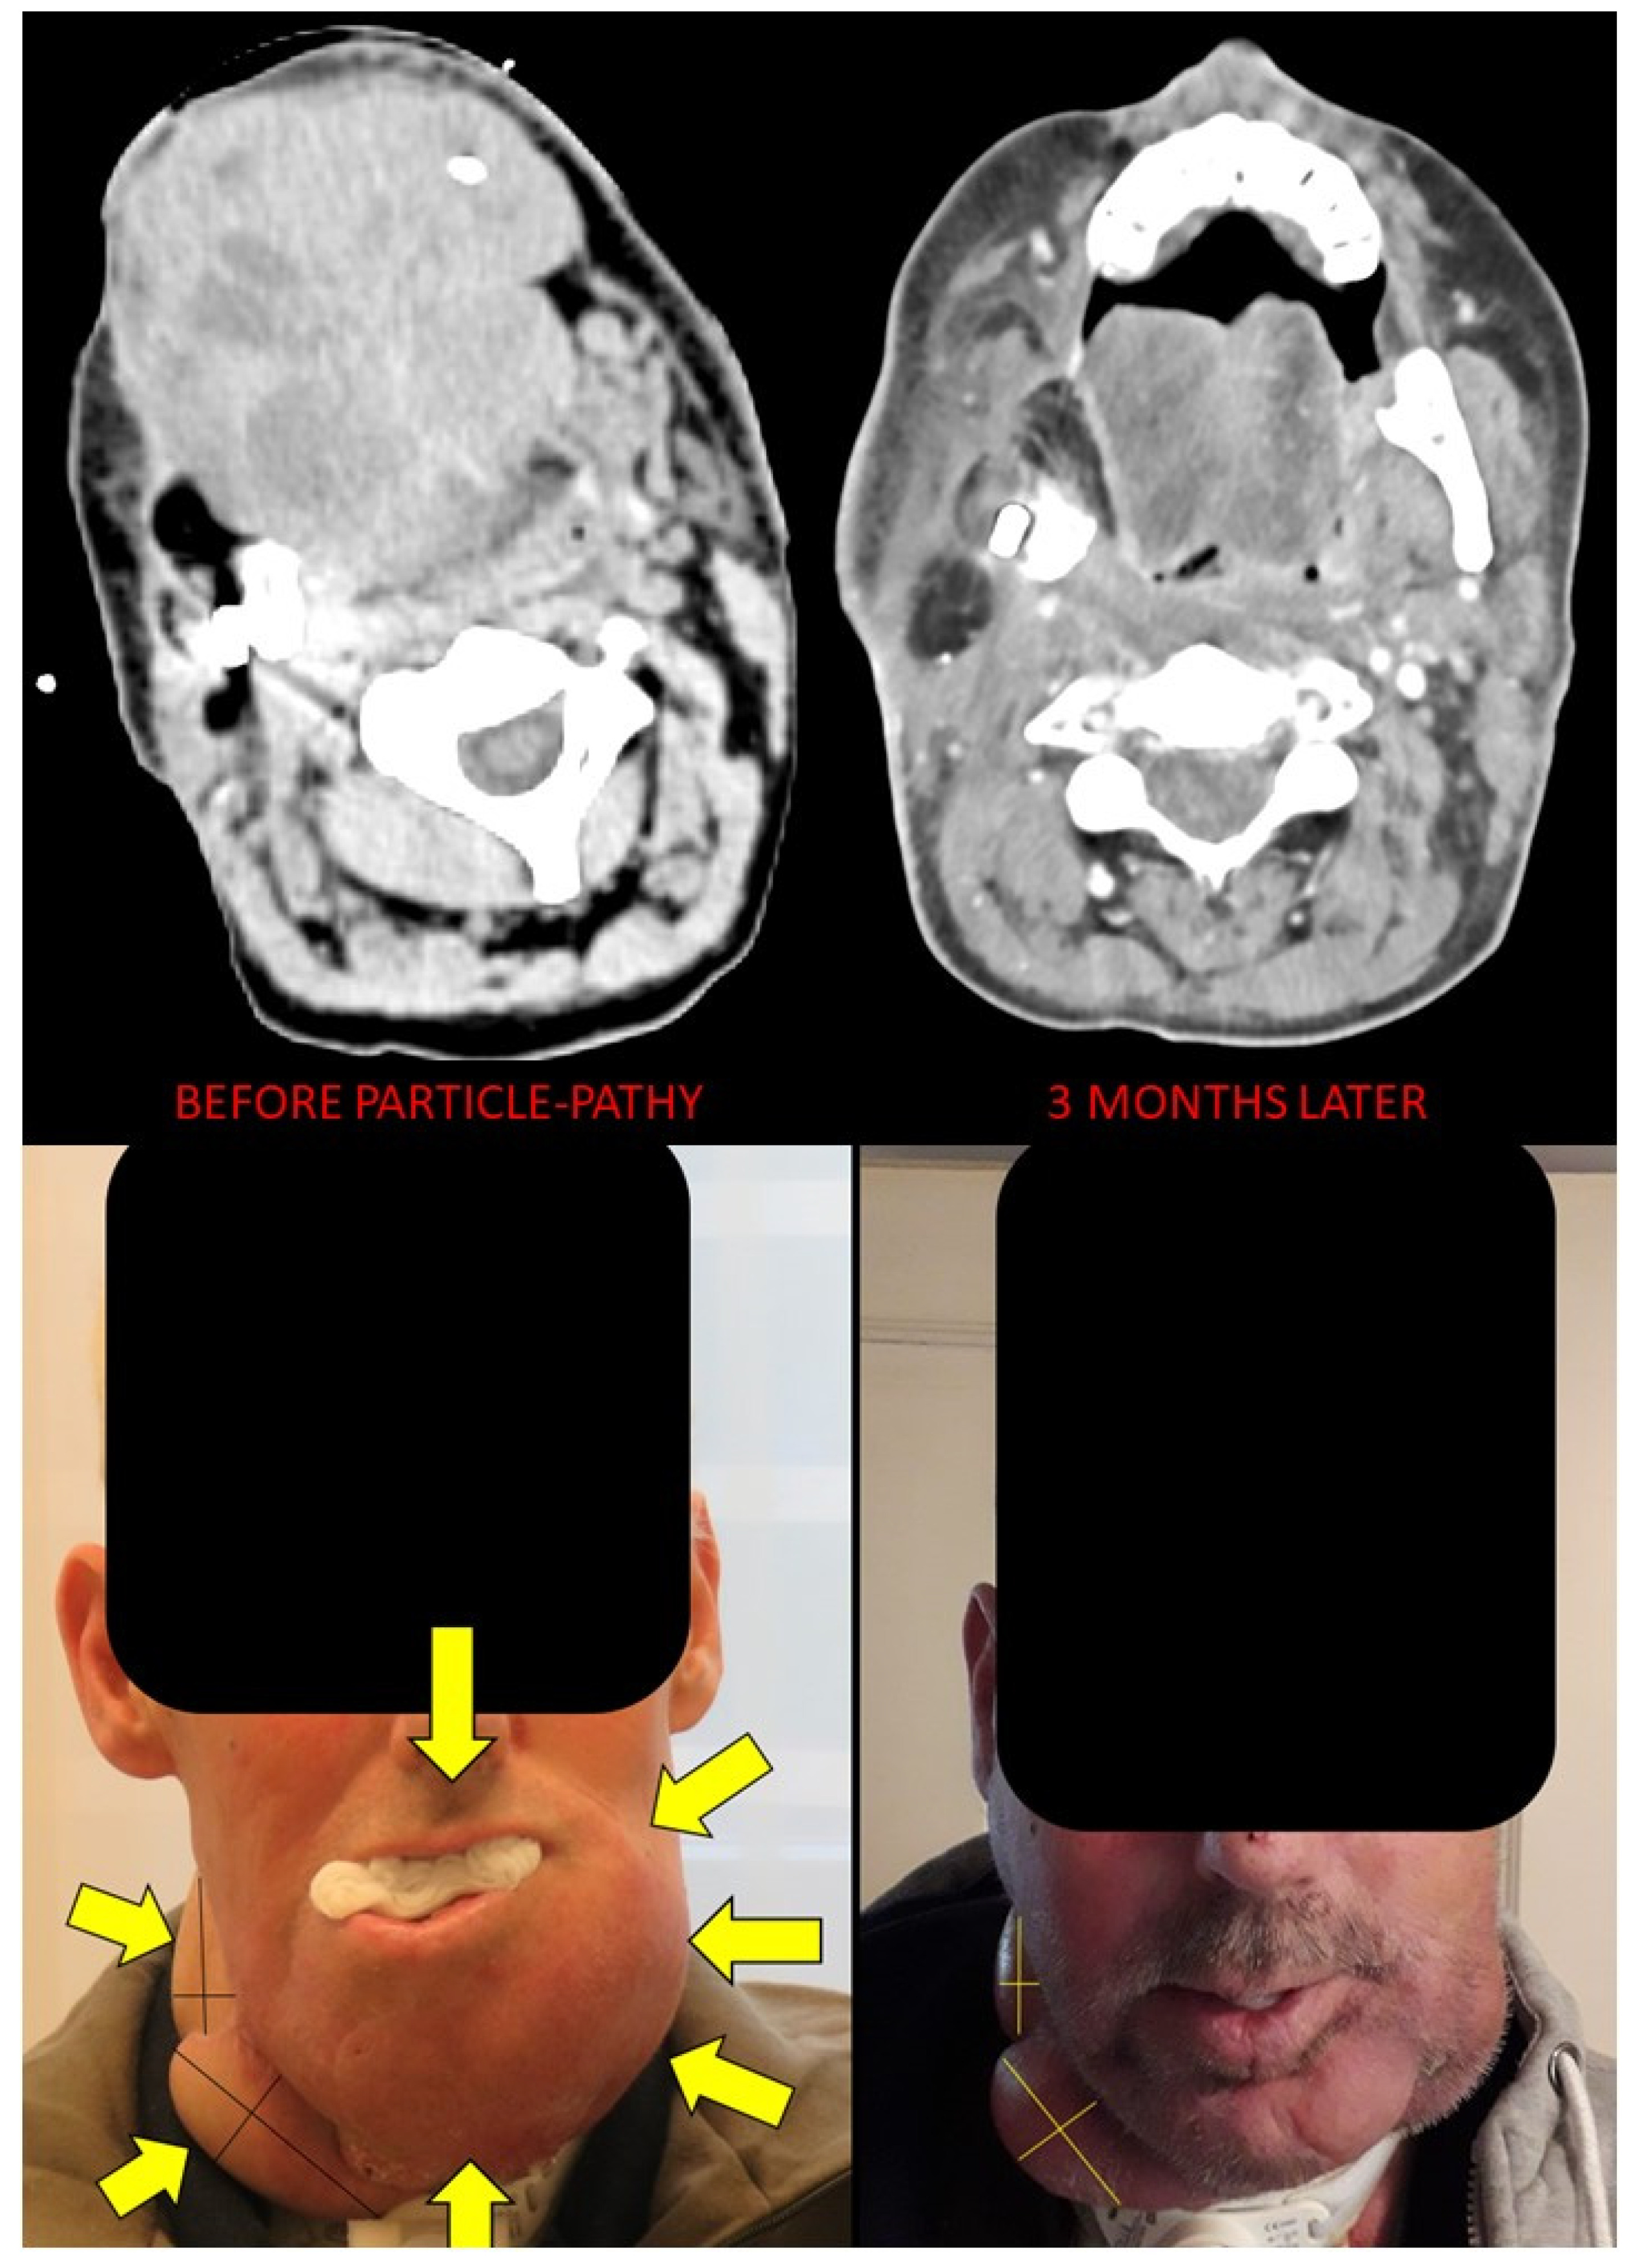

Figure 6. Bystander and abscopal effects generated by Particle-PATHY: figure shows the almost complete disappearance of partially irradiated recurrent squamous cell bulky tumor of the oral cavity due to the bystander effect and regression of unirradiated right neck lymph node metastases due to the abscopal effect three months following Particle-PATHY (left: before Particle-PATHY; right: after). This patient was previously already irradiated with 70 Gy external beam radiotherapy and could not be re-irradiated either with conventional photon nor with particle therapy.